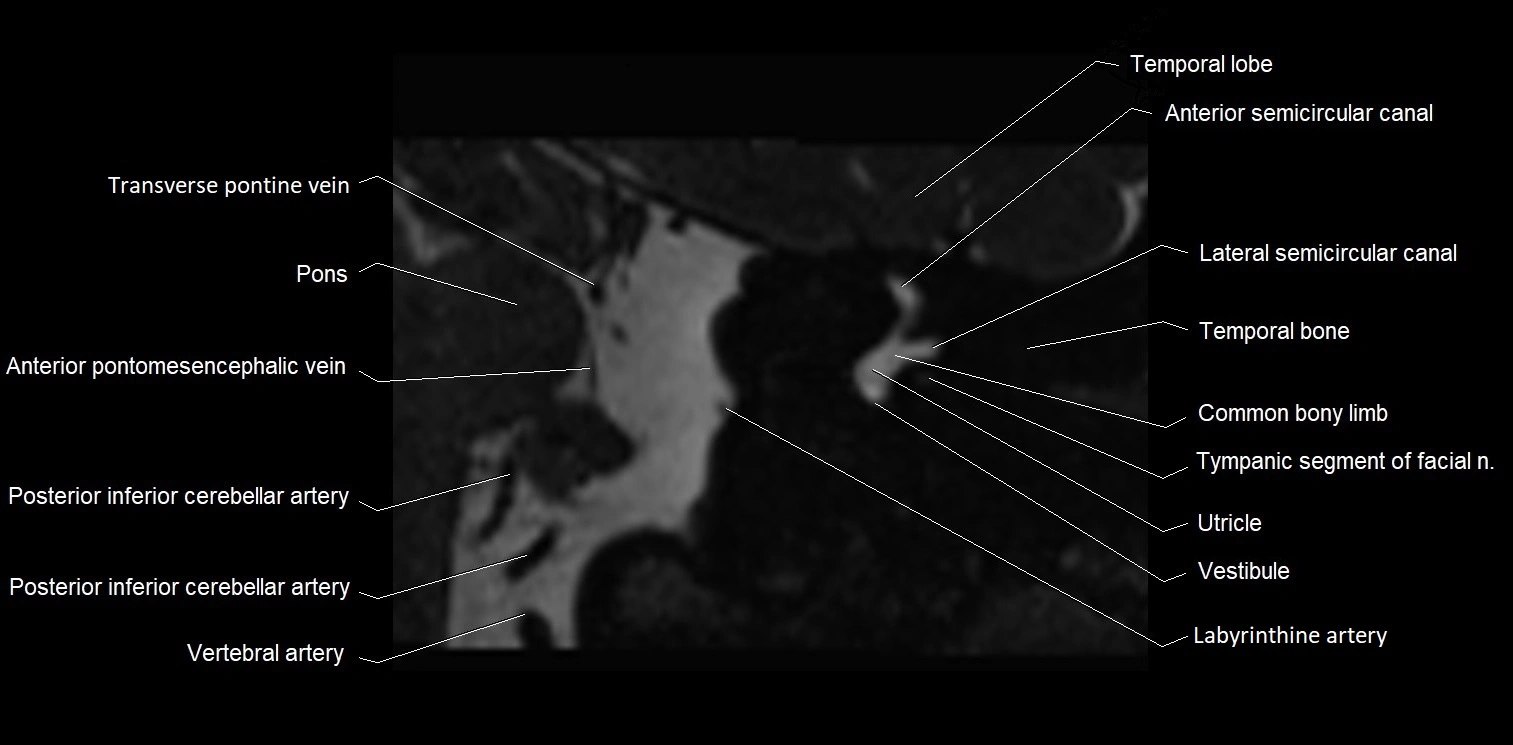

MRI Appearance

• The abducens nerve is a small, thin, linear structure

• Best visualized on high-resolution T2-weighted 3D MRI sequences (e.g., FIESTA or CISS)

• Seen as a hypointense (dark) line running from the brainstem at the pontomedullary junction, traversing the prepontine cistern, and entering Dorello’s canal under the petrosphenoidal ligament, then into the cavernous sinus, and finally the orbit

• May be challenging to visualize in standard MRI due to its small size

• Pathology may be inferred by absence, displacement, or enhancement of the nerve